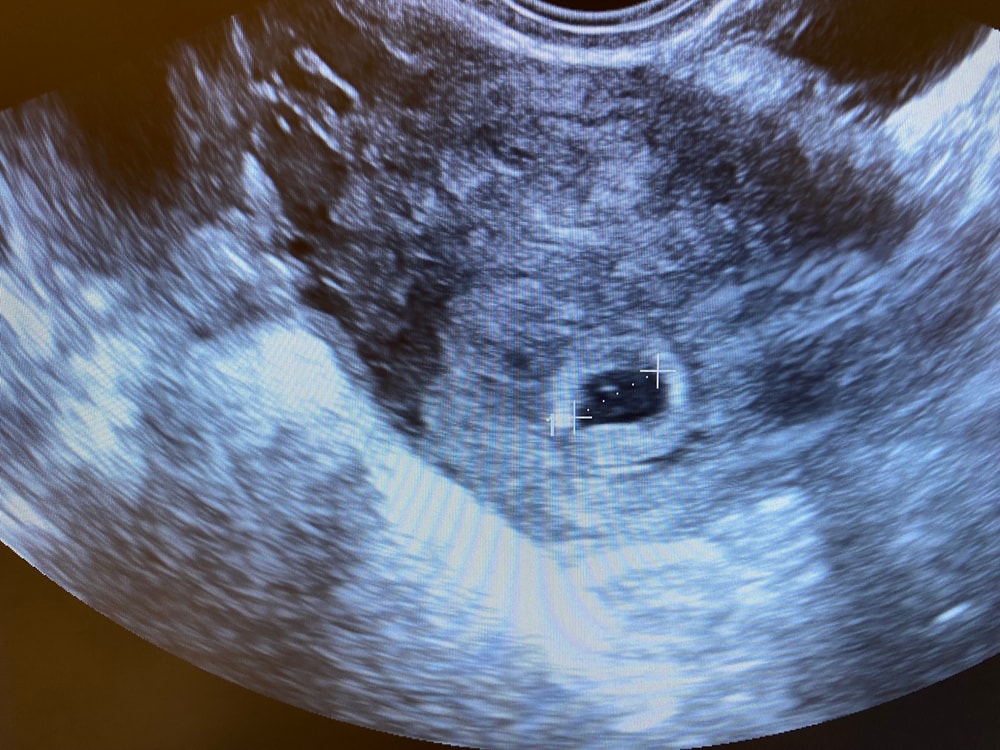

Чудо 39, да, это снимок 4 недель 6 дней. А вот снимок 6.6 недель Изображение

Чудо 39, КТР 8.5 мм был